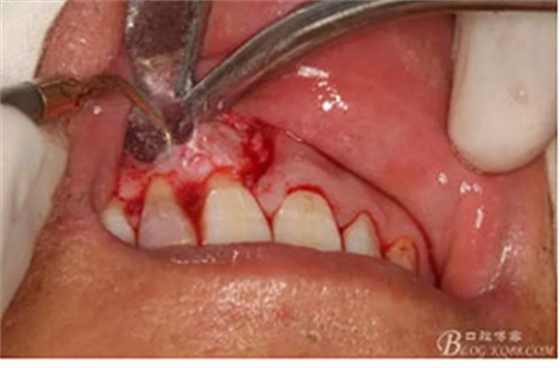

圖13.囊壁摘除后形成的骨腔,12牙根完全裸露在骨腔內(nèi)。

圖14.超聲骨刀切除根尖組織3mm。